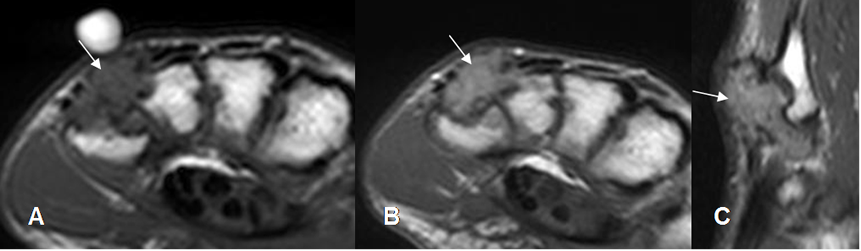

Fig 124 C. Tumor de células gigantes.

A: RM axial, B y C: RM axial y sagital con contraste. Igual paciente anterior. La lesión de tejidos blandos realza con el contraste.